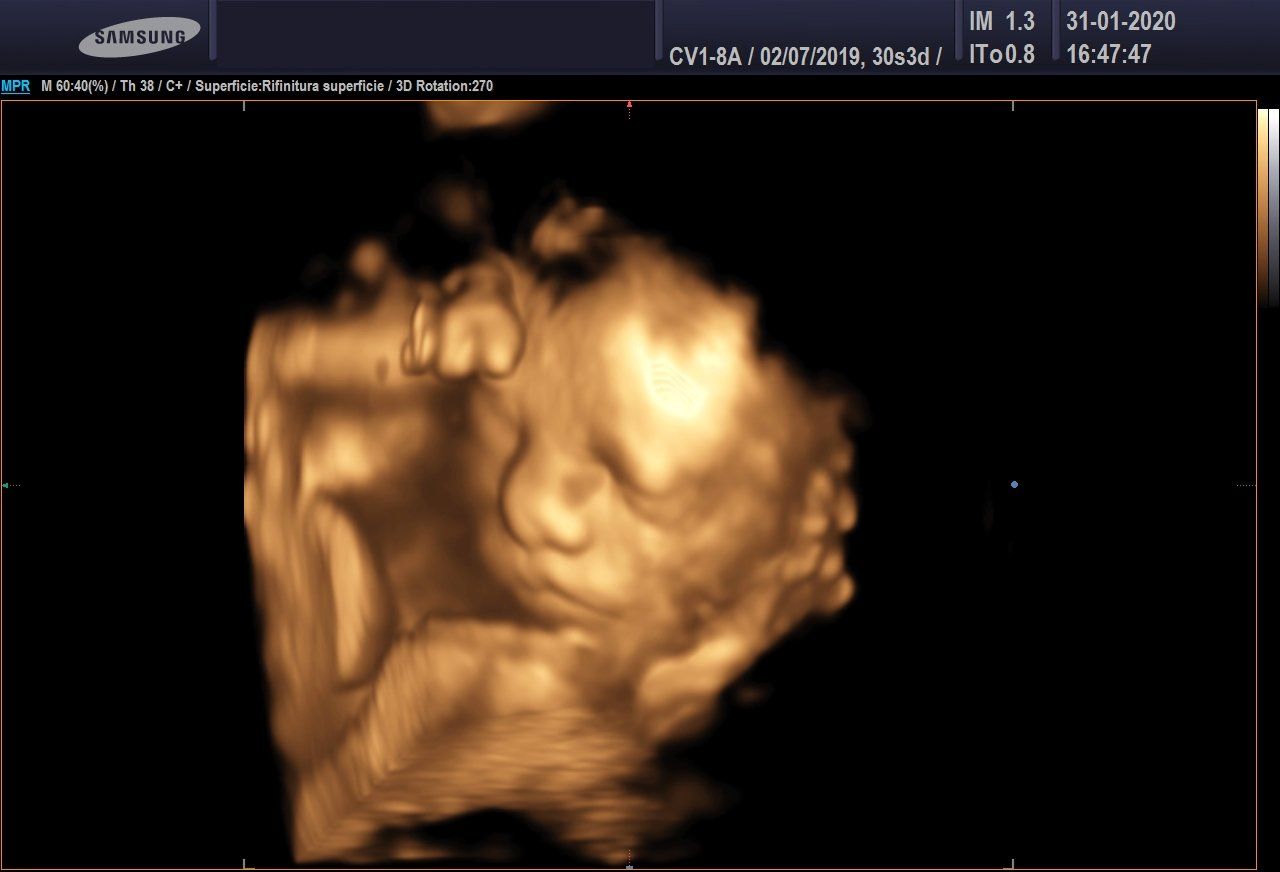

Ecografia 3D/4D

L'ecografia 3D consente di ottenere delle immagini statiche, non in movimento, ma in pratica delle foto delle fattezze del feto.

Nel suo studio di ginecologia, anche per conto di colleghi, il dott. Di Leo esegue ecografie morfologiche per lo studio delle malformazioni fetali.